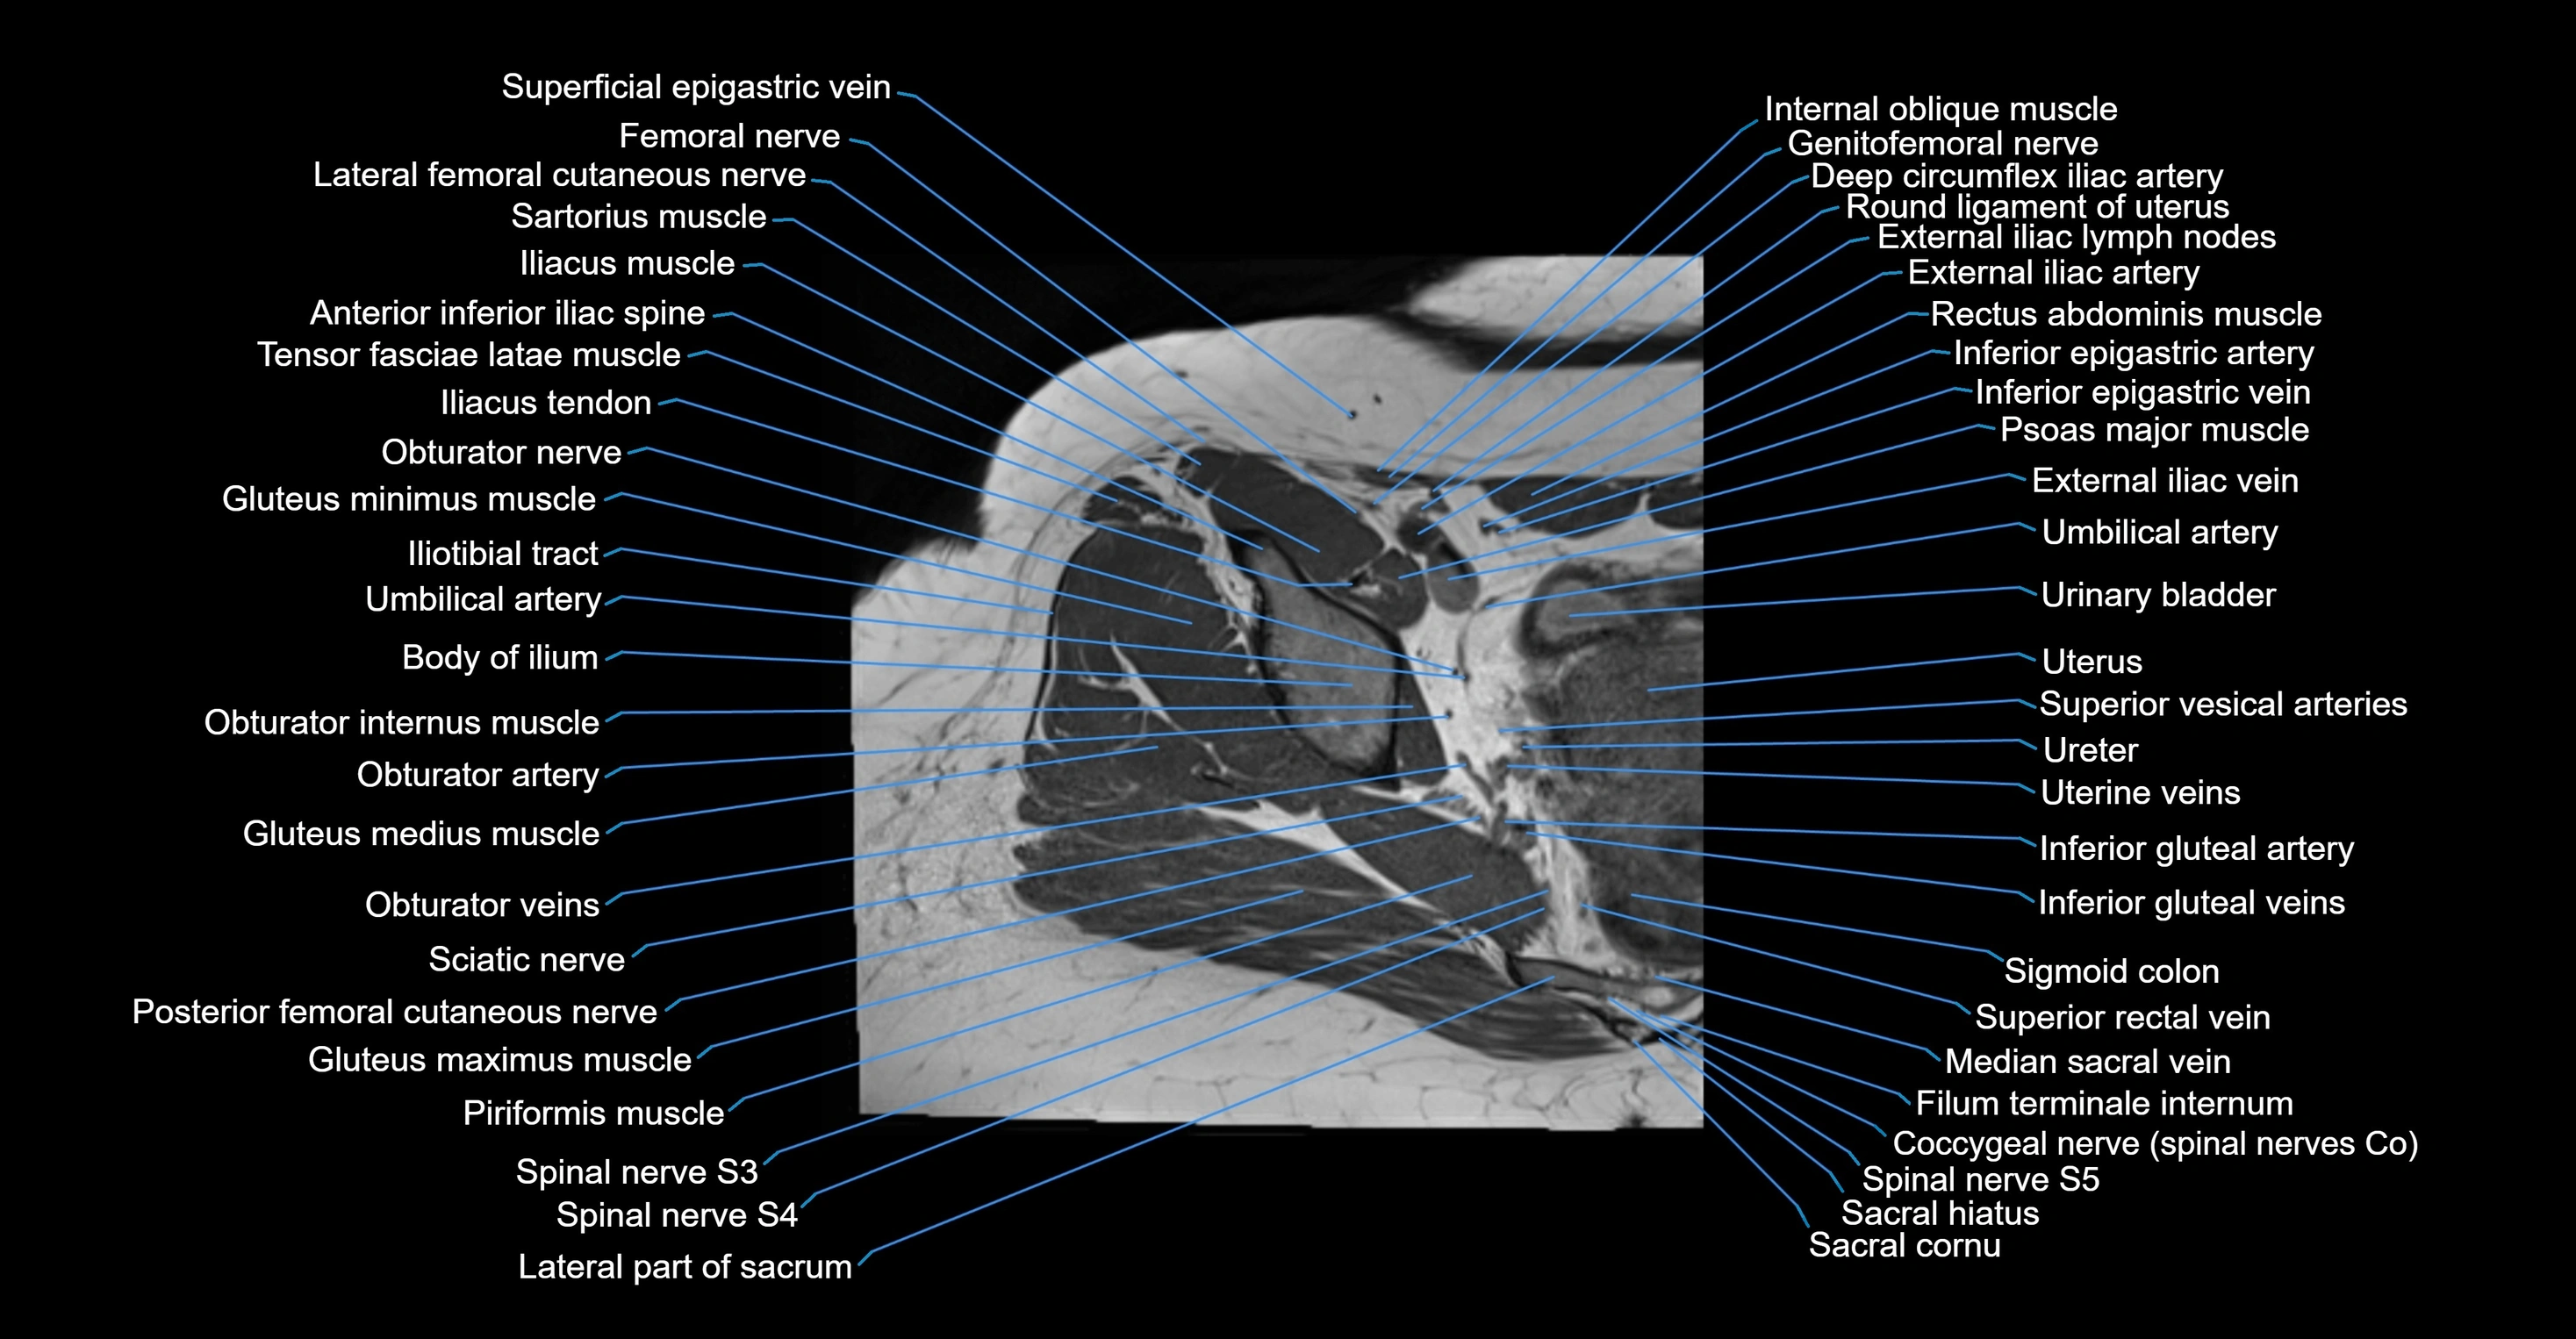

- Anterior inferior iliac spine

- Body of ilium

- Deep circumflex iliac artery

- External iliac artery

- External iliac lymph nodes

- External iliac vein

- Femoral nerve

- Genitofemoral nerve

- Gluteus maximus muscle

- Gluteus medius muscle

- Gluteus minimus muscle

- Iliotibial tract

- Inferior epigastric artery

- Inferior epigastric veins

- Inferior gluteal artery

- Inferior gluteal vein

- Lateral femoral cutaneous nerve

- Median sacral vein

- Obturator internus muscle

- Posterior femoral cutaneous nerve

- Psoas major muscle

- Round ligament of uterus

- Sacral hiatus

- Sacral cornu (sacral horn)

- Sigmoid colon

- Spinal nerve S1

- Spinal nerve S2

- Spinal nerve S3

- Spinal nerve S4

- Spinal nerve S5

- Superior rectal vein

- Superior vesical artery

- Tensor fasciae latae muscle

- Umbilical artery

- Urinary bladder

- Uterus